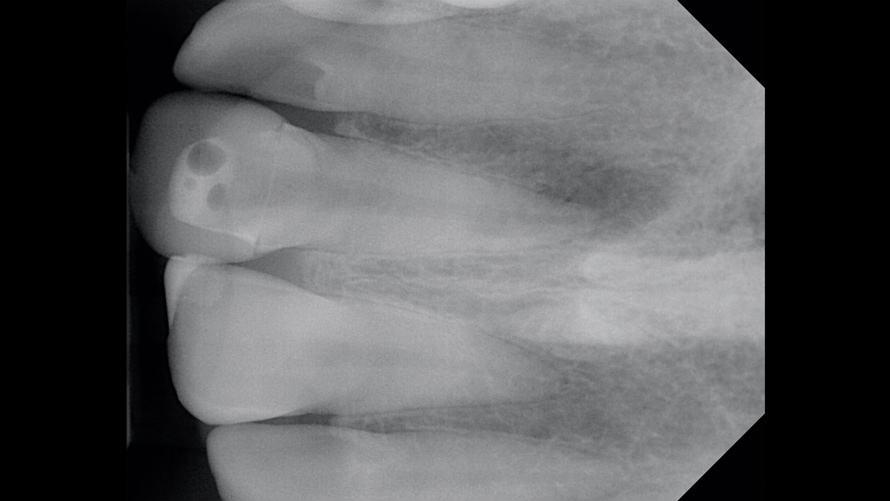

(4.) Case 2: Preoperative radiograph of the maxillary left central incisor, demonstrating existing nonsurgical root canal therapy.

Figure 4

In the second case, a preoperative periapical radiographic examination revealed that the patient had previously undergone nonsurgical root canal therapy and that the existing root-filling material stopped 3 mm to 4 mm short of the apex (Figure 4). Further examination revealed an intact lamina dura and normal bone trabeculation. Under high-power microscope magnification, the existing root canal sealer appeared to be the cause of the intrinsic staining; therefore, it was deemed necessary to re-treat and refill the existing root canal.